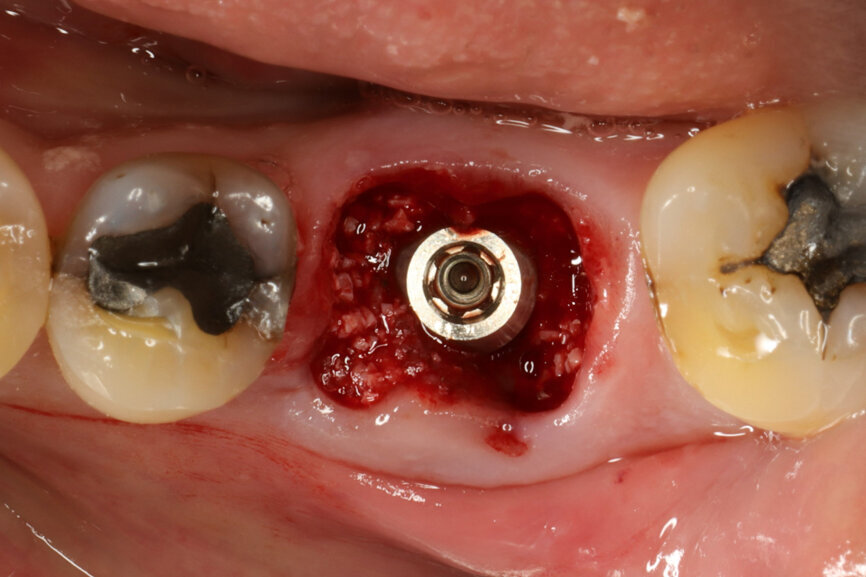

Fig. 14: Implant in final position with bone augmentation.

Fig. 15: Implant in final position with A-PRF protecting the bone substitute granules.

It was possible to verify solid interradicular bone availability (Fig. 5), extending further the limits of the root apices and allowing for a centrally oriented osteotomy. The implant bed preparation started with the use of a needle drill at 800 rpm, followed by the ⌀ 2.2 mm and ⌀ 2.8 mm drills (Figs. 6–10). The implant was placed with the use of ratchet and torque control, reaching the desired final position at a 50 N cm torque value (Figs. 11–13). The socket was then augmented with bovine-derived bone substitute impregnated with advanced platelet-rich fibrin (A-PRF) and finalised with sutures to keep the A-PRF application immobile, and a 3 mm healing abutment was placed (Figs. 14–17).